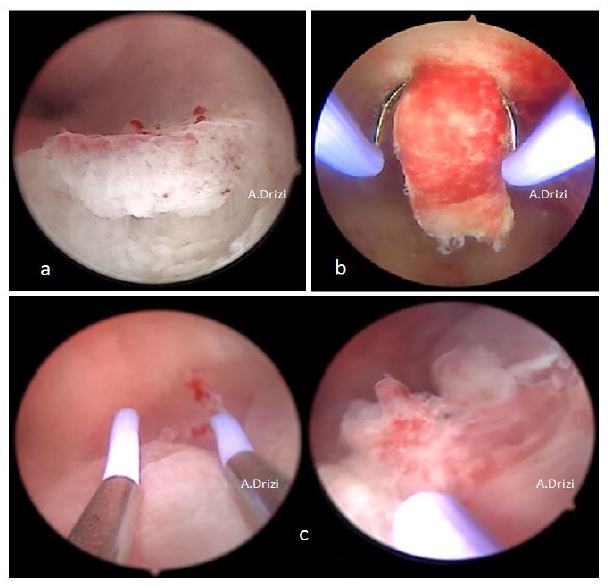

Figure 8. Targeted sampling performed within the endometrial areas displaying dysfunctional signs: a: micropolyps and hyperemia; b: strawberry pattern (with the loop); micropolyp+ irregular thickness and gland distribution (with the loop).

Figure 10. Consensually accepted signs for adenomyosis. a: debossed patterns: focal defect in atrophic endometrium; b: focal defect surrounded by strawberry aspect; c:fibrous cystic appearance of intrauterine lesions; d: hypervascularity; e: submucosal hemorrhagic cyst displaying a blue color, releasing a chocolate brown fluid after incision.